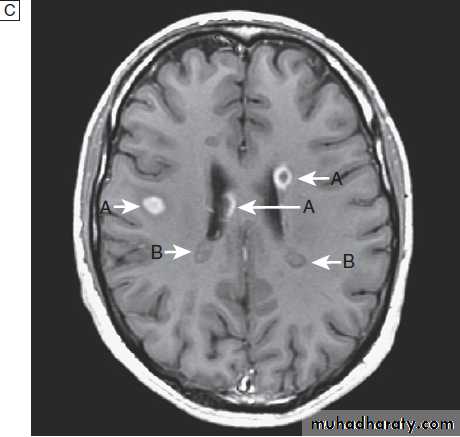

Fig. Different techniques of imaging the head and brain. A Skull X-ray showing lytic skull lesion (eosinophilic granuloma – arrow). B CT

showing complete middle cerebral artery infarct (arrows). C MRI showing widespread areas of high signal in multiple sclerosis (arrows). D SPECT after

caudate infarct showing relative hypoperfusion of overlying right cerebral cortex (arrows).